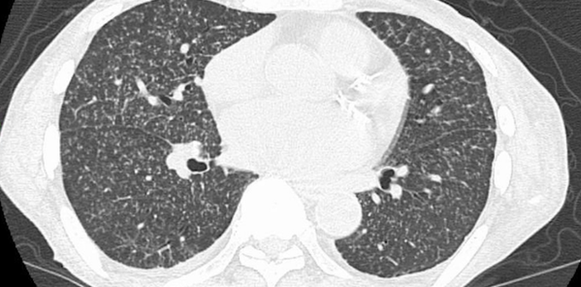

CTでは小粒状影が多発していることが分かります。なぜこれを粟粒結核と疑えるかというと、ぞくりゅ結核は2mm程度の粒で、サルコイドーシスは5mmくらいの粒だからです。

三連痰を施行し、結核が検出されるか確認する必要があります(通常はこの時点で結核疑いで結核病院に紹介します)。